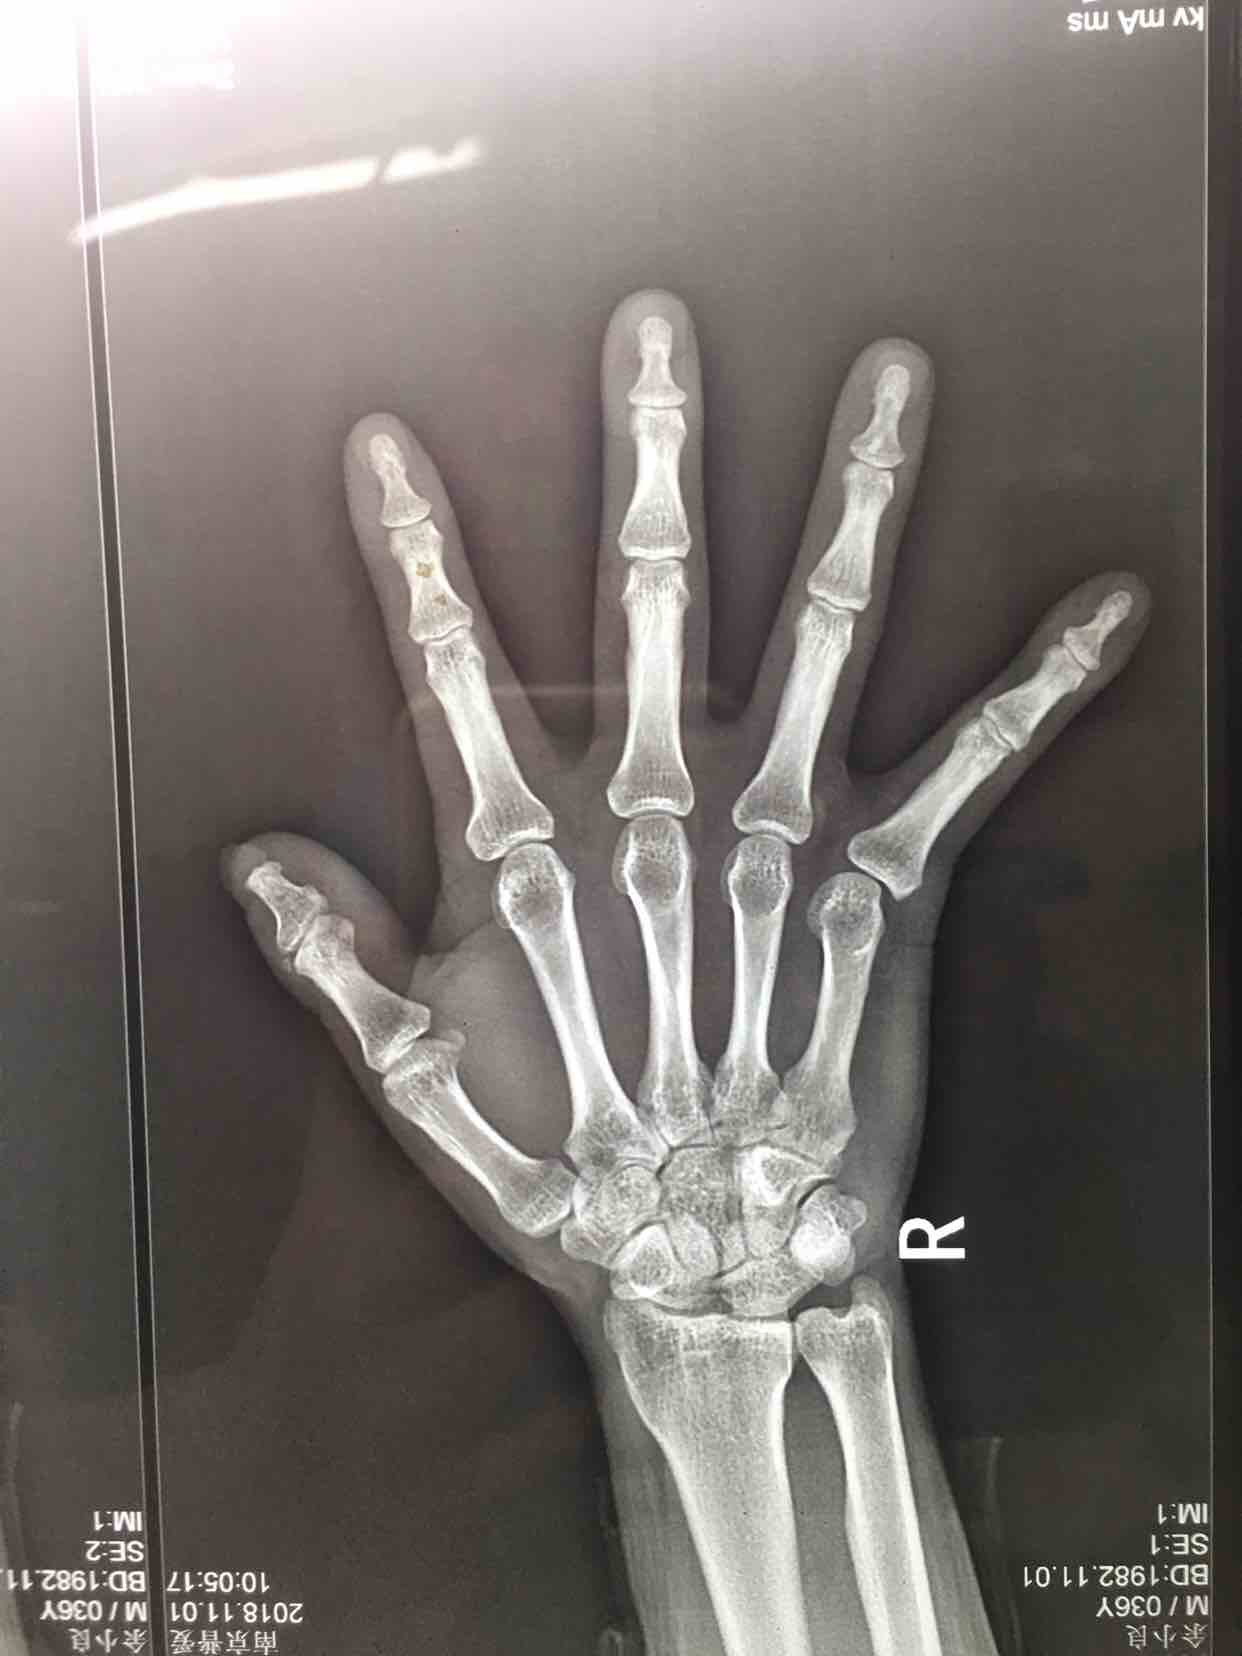

锤状指(切复内固定术)

锤状指

摔伤后右小指肿胀,畸形14天。既往身体健康,无特殊不良嗜好。

生命体征平稳,右小指肿胀,畸形,局部皮色皮温基本正常,伸指功能障碍,屈指正常,末梢血运感觉正常。

完善术前准备,在指神经阻滞麻醉下行切复内固定术,术后制动4-6周,预防感染等处理。